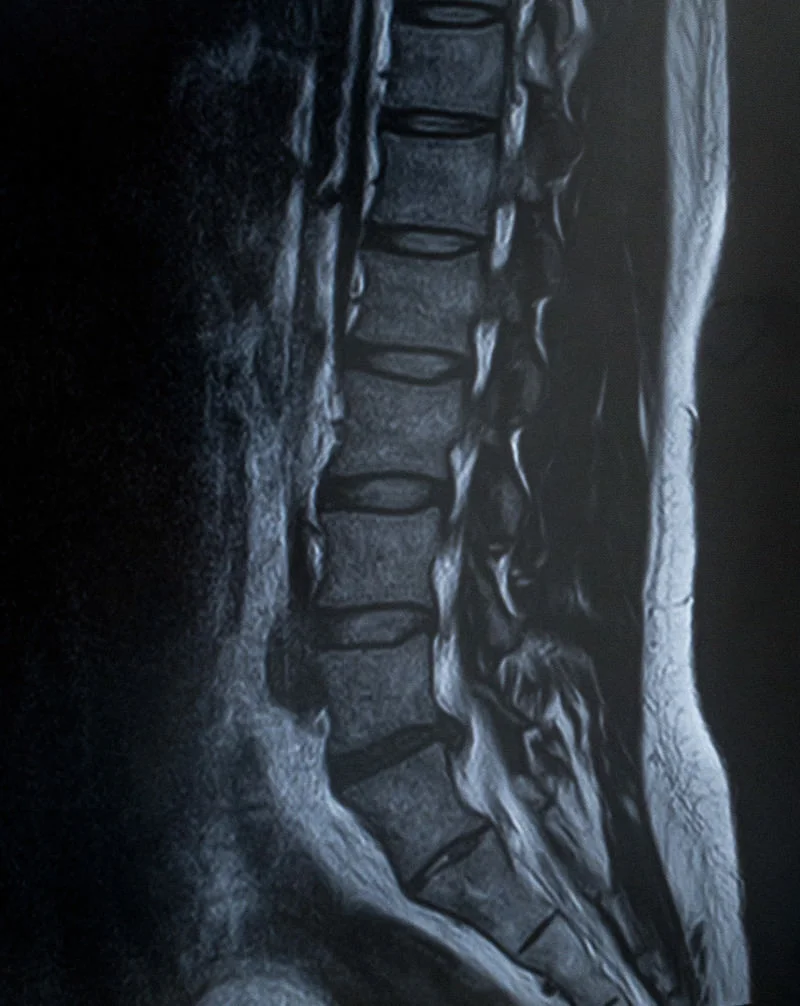

腰椎椎間板ヘルニアは、

腰の骨と骨の間にある椎間板が変形・突出して

神経を圧迫することで起こる症状です。